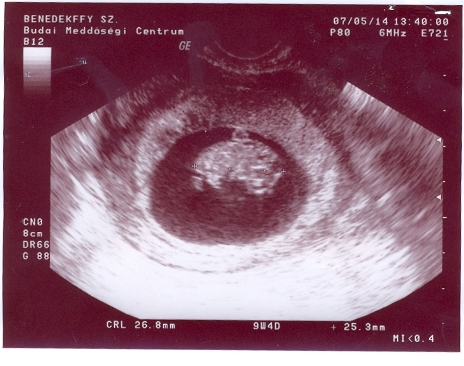

A baba:26,8mm-es B baba:25,3mm-es!Pont koruknak megfelelő!Holnap vagy este rakok fel képet!Mozgott a kezük ezerrel!Édesek voltak!

Kép Kép

Ezek az én drágáim!!!!!!